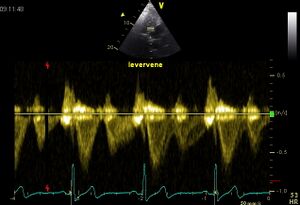

Flow pattern

Because in most cases VCI is perpendicular to the beam in the ultrasound image running, the flow pattern of the hepatic vein viewed . This is the same as VCI, only the hepatic vein is parallel to the sound beam .

Levervene02.jpg Hepaticveinrefersal01.jpg

Normal hepatic vein flow Systolic flow reversal of the hepatic vein in severe TI1